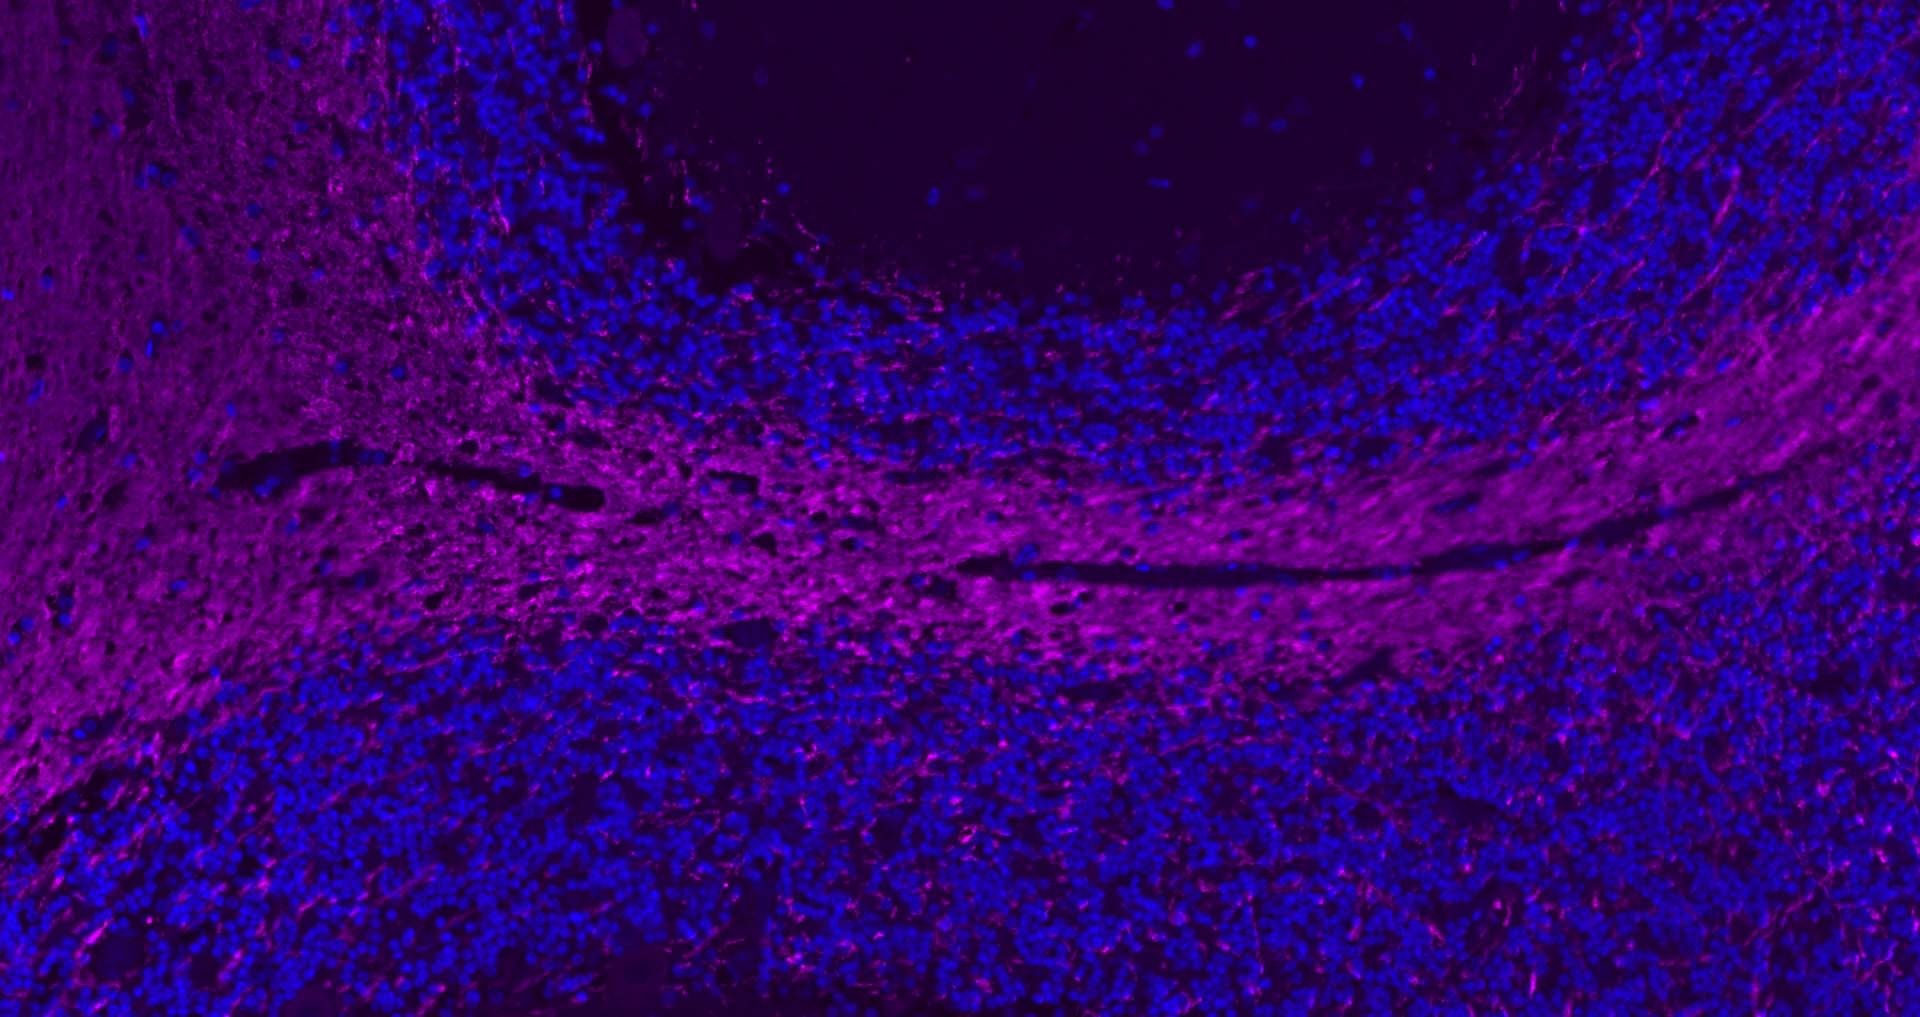

6. Paraformaldehyde-fixed, paraffin embedded Rat Cerebellum; Antigen retrieval by boiling in sodium citrate buffer (pH6.0) for 15 min; Antibody incubation with MBP Polyclonal Antibody, Unconjugated (TMAB-01110) at 1:200 overnight at 4°C. Followed by conjugated Goat Anti-Rabbit IgG antibody (Purple), DAPI (blue) was used to stain the cell nucleus.

7. Paraformaldehyde-fixed, paraffin embedded Human Cerebellum; Antigen retrieval by boiling in sodium citrate buffer (pH6.0) for 15 min; Antibody incubation with MBP Polyclonal Antibody, Unconjugated (TMAB-01110) at 1:200 overnight at 4°C. Followed by conjugated Goat Anti-Rabbit IgG antibody (Purple), DAPI (blue) was used to stain the cell nucleus.

8. Paraformaldehyde-fixed, paraffin embedded Human Left Parietal Lobe; Antigen retrieval by boiling in sodium citrate buffer (pH6.0) for 15 min; Antibody incubation with MBP Polyclonal Antibody, Unconjugated (TMAB-01110) at 1:200 overnight at 4°C. Followed by conjugated Goat Anti-Rabbit IgG antibody (Purple), DAPI (blue) was used to stain the cell nucleus.

9. Paraformaldehyde-fixed, paraffin embedded Mouse Cerebrum; Antigen retrieval by boiling in sodium citrate buffer (pH6.0) for 15 min; Antibody incubation with MBP Polyclonal Antibody, Unconjugated (TMAB-01110) at 1:200 overnight at 4°C. Followed by conjugated Goat Anti-Rabbit IgG antibody (Purple), DAPI (blue) was used to stain the cell nucleus.

10. Paraformaldehyde-fixed, paraffin embedded Mouse Cerebellum; Antigen retrieval by boiling in sodium citrate buffer (pH6.0) for 15 min; Antibody incubation with MBP Polyclonal Antibody, Unconjugated (TMAB-01110) at 1:200 overnight at 4°C. Followed by conjugated Goat Anti-Rabbit IgG antibody (Purple), DAPI (blue) was used to stain the cell nucleus.